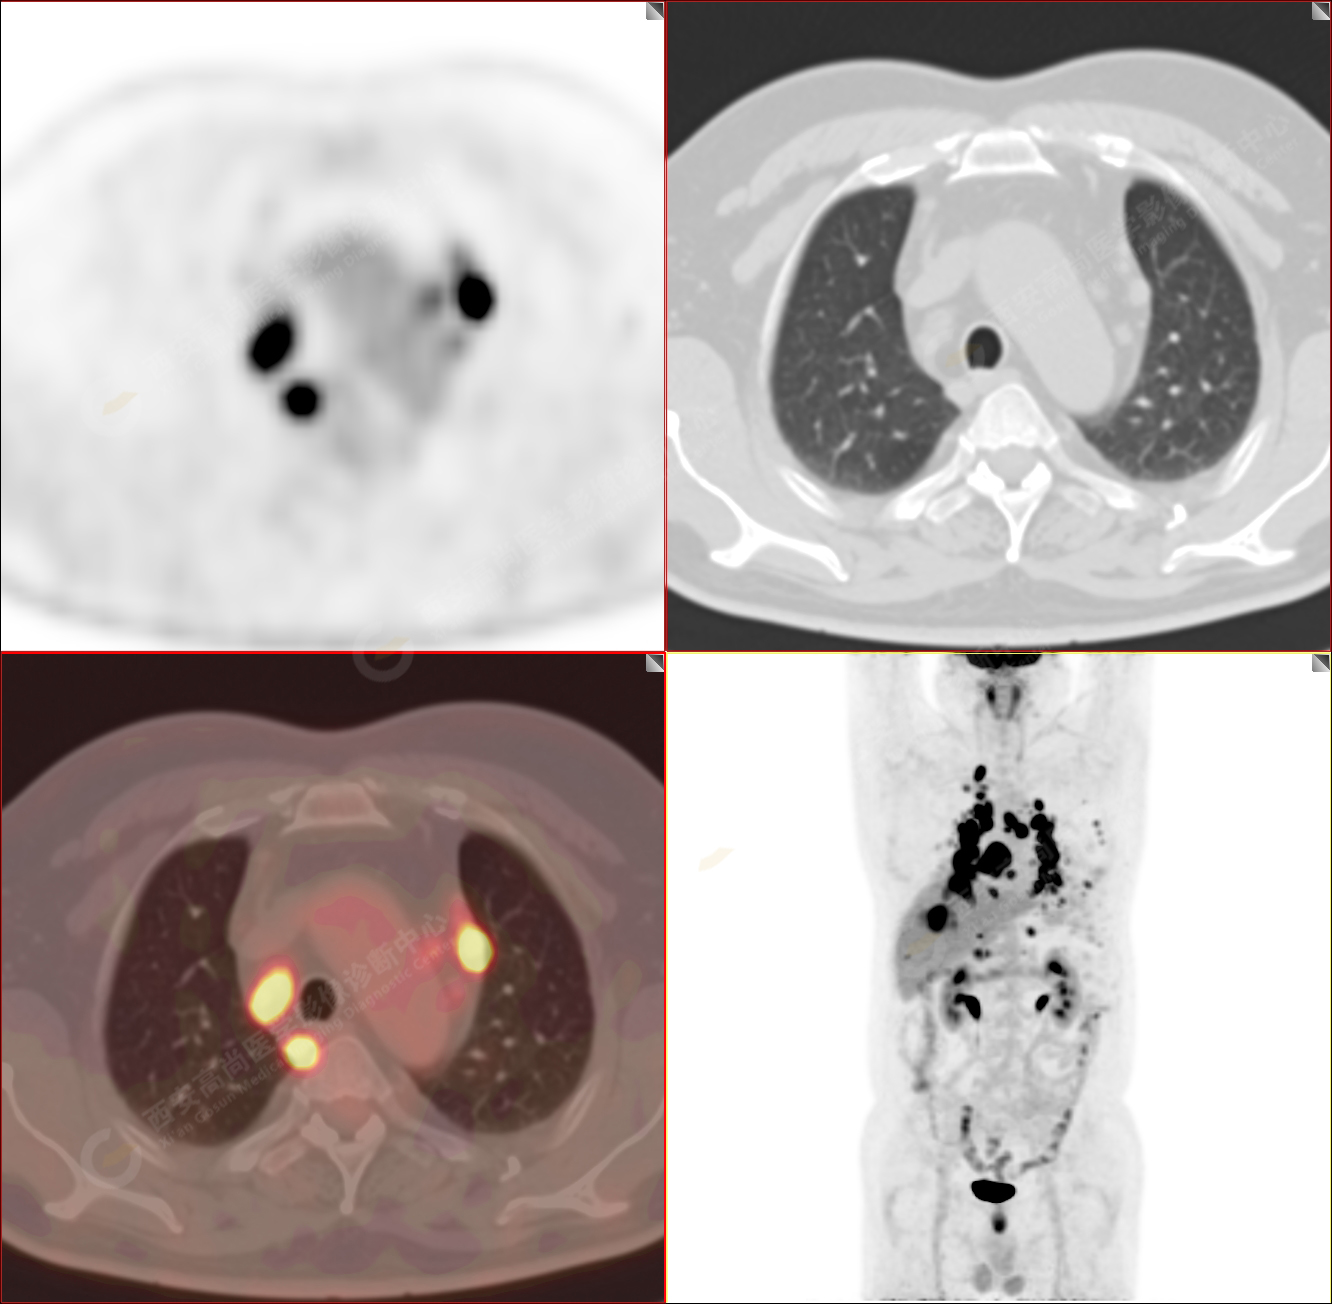

PET/CT-MR診斷結(jié)節(jié)病雙肺及全身多發(fā)淋巴結(jié)廣泛累及1例【西安高尚病例】

男性,53歲,頭暈半月入院,CT發(fā)現(xiàn)肺內(nèi)腫塊,雙肺多發(fā)大小不等實(shí)性及粟粒樣結(jié)節(jié),雙肺門(mén)及縱隔多發(fā)腫大淋巴結(jié)。病程中無(wú)發(fā)熱、胸悶氣及胸部不適。既往:左側(cè)肋骨外傷史。

PET/CT圖像